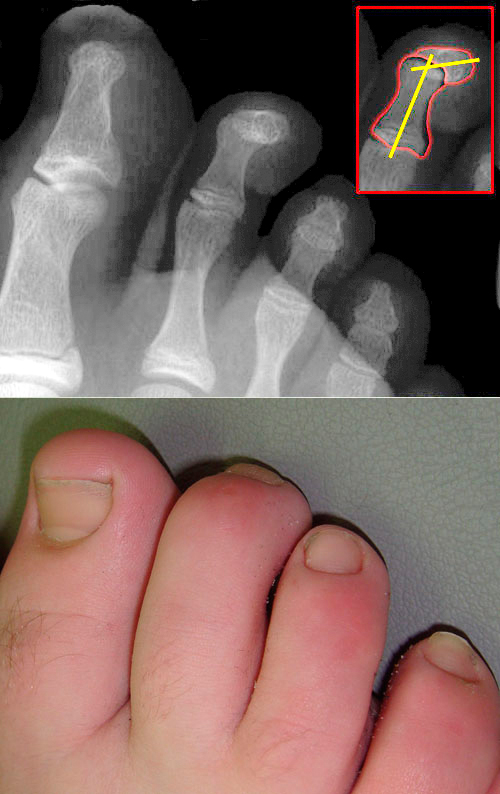

Die Form einer Hammerzehe (Digitus malleus) ergibt sich durch die permanente krallenartige Beugung einer Zehe. Man unterscheidet flexible und fixierte Hammerzehen. Sie ist differentialdiagnostisch von der Kamptodaktylie abzugrenzen und meistens aufgrund der Verwendung ungeeigneten Schuhwerks mechanisch bedingt. Auch neurologische Erkrankungen können zu diesem Symptom führen.

Die Indikation hierfür besteht, wenn sich die Zehenstellung passiv korrigieren lässt.

Kontraindikation für eine operative Sanierung stellt die schlechte Durchblutung (pAVK) dar. Postoperativ ist meist Vollbelastung in steifer Sohle erlaubt; die Entfernung der Fäden kann nach zwei Wochen erfolgen. Als Komplikationen können Wundheilungsstörungen, Durchblutungsstörungen oder Nekrosen auftreten.